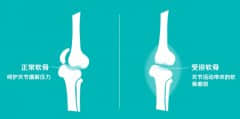

膝关节骨性关节炎的临床表现